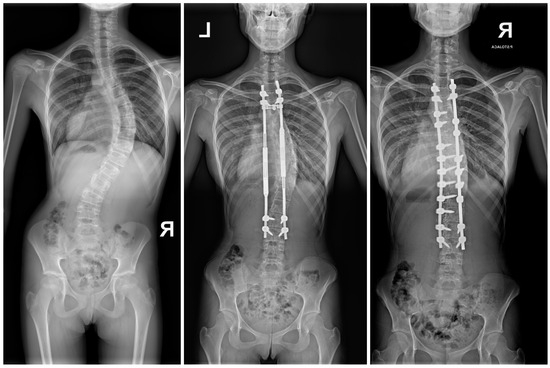

2.3. Surgical Technique and Postoperative Use of MCGRs